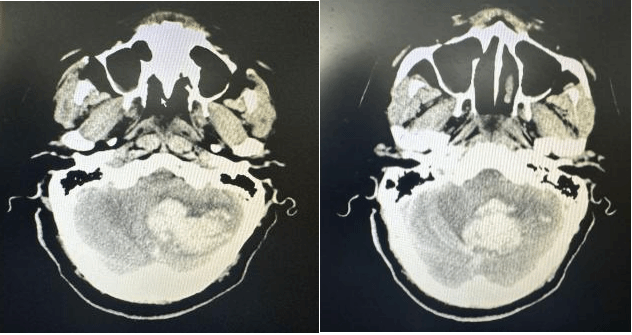

面对此例极危重患者,急诊医学科团队在患者到院第一时间立即启动最高级别卒中/脑出血救治绿色通道。紧急气管插管,同时建立静脉通路开通急救通道,在维持患者基础生命支持的同时,同步联系影像科。医学影像科“绿色通道”立即响应,CT扫描快速完成。神经外科值班医师火速阅片,明确诊断:小脑大量出血(37.3ml)破入第四脑室,脑疝形成、脑干受压、梗阻性脑积水。小脑出血量远超手术指征的警戒线,死亡率极高,每一分钟的延误,都可能意味着死亡和不可逆的脑干功能衰竭……

术前CT